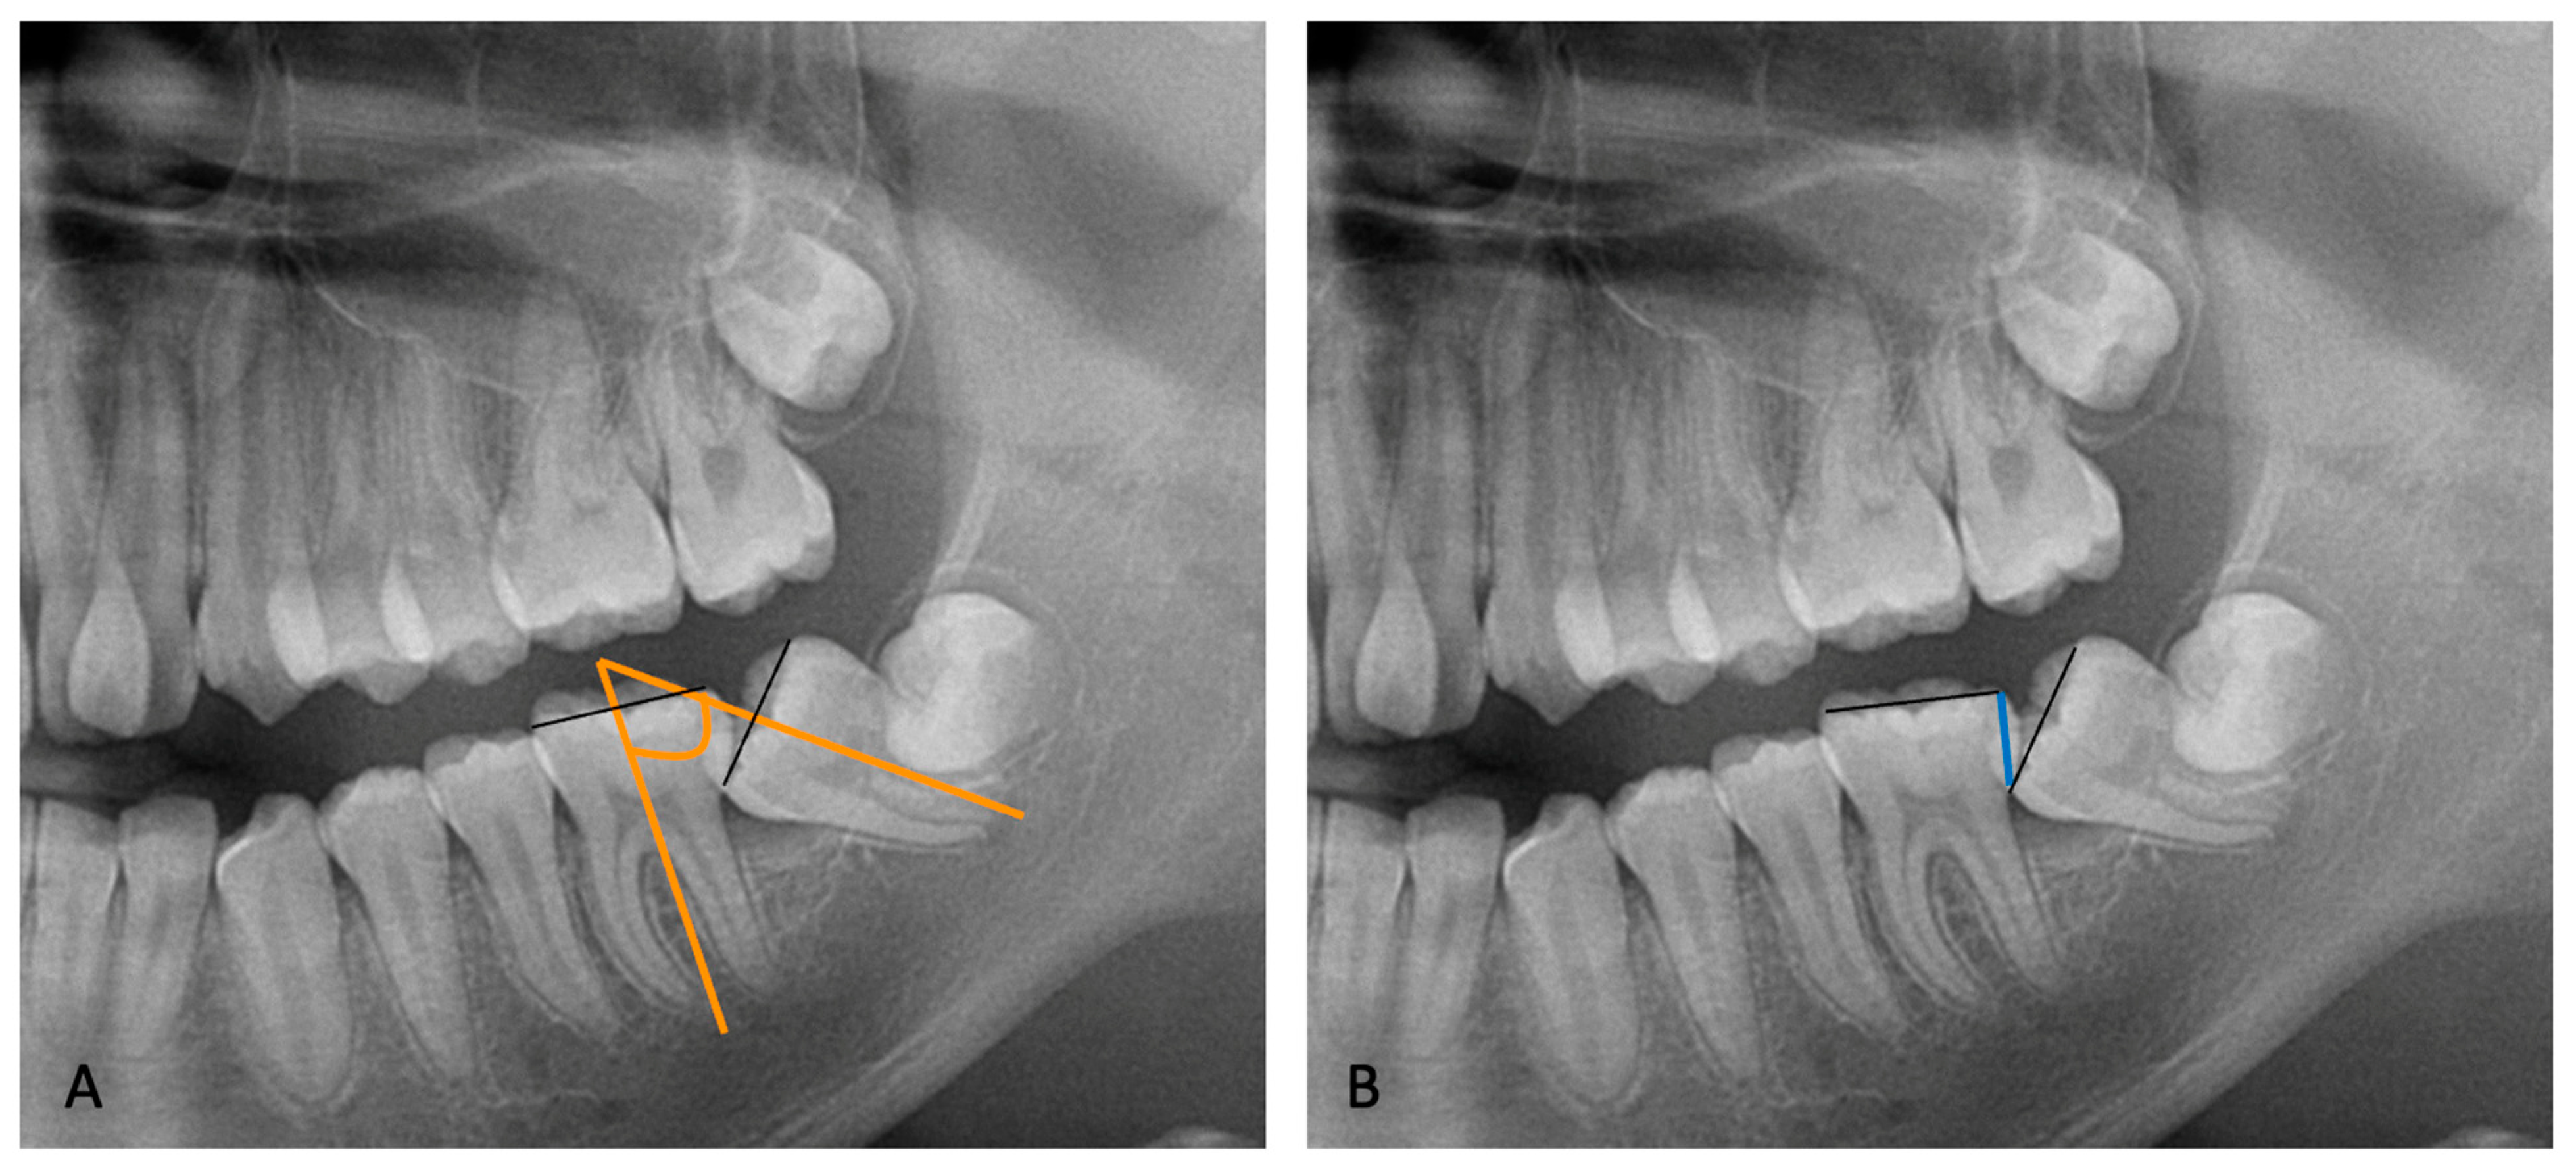

A mucoperiosteal flap was elevated without releasement incisions, which extended from the mandibular first molar to the retromolar area on both the buccal and lingual sides. In all the patients of both groups, the procedure involved the exposure of the crown of MM2 and germectomy of the third molar. In the subjects treated with the traditional technique (Group A), a gentle luxation of MM2 was performed and a 0.6 mm double-twisted brass wire was inserted under the contact point between the first and second mandibular molars (Figure 2).

In the subjects treated with skeletal anchorage (Group B), after the germectomy of the third molar, a self-drilling miniscrew (BENEfit, psm, Tuttlingen, Germany) was inserted in the retromolar area just distal to the post-extraction socket of the third molar using a surgical contra-angle (iSD900; NSK, Tochigi, Japan) with torque control (maximum torque set at 40 N/cm). The insertion site and angle, as well as the length and diameter of the miniscrew, were planned before the procedure through measurements from orthopantomography. After the miniscrew insertion, two orthodontic brackets were applied to the molar crown, one on the vestibular surface and one on the lingual surface. Finally, an elastic chain was attached to the miniscrew head and the orthodontic brackets to create an elastic sling. Once the primary miniscrew stability and the effectiveness of the elastic sling traction (the elastic chain was elongated to about twice its original length) were both verified, the surgical site was completely sealed with submerged traction using sutures (Figure 3).

Figure 2. Surgical procedure with brass wire used in Group A subjects. (A): mucoperiosteal flap and the exposure of the impacted second molar; (B): the exposure of the third molar; (C): the germectomy of the third molar; (D): the application of brass wire; (E): suture.

Figure 3. Surgical procedure using skeletal anchorage in Group B subjects. (A): mucoperiosteal flap and the exposure of the impacted second molar; (B): the exposure of the third molar; (C): the germectomy of the third molar; (D): miniscrew insertion; (E): the application of orthodontic brackets on the buccal and lingual surface of the mandibular second molar; (F): the application of the elastic chain.